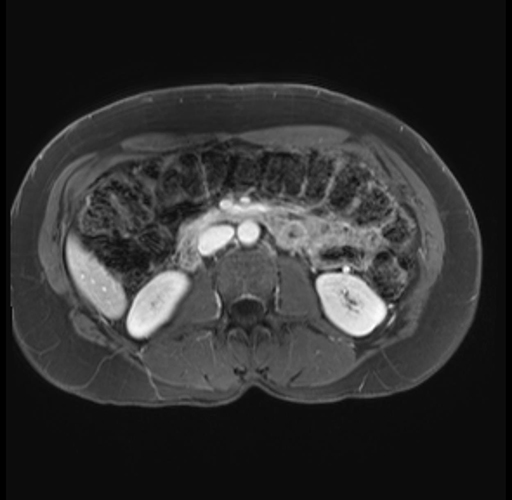

Imaging Analysis

Look through the patient's CT scan to identify any areas of concern for the necessary procedure.

Based on your CT findings, which issue(s) are present and would give reason for "planned slowing down moment(s)" in this case?

Considering a standard distal pancreatectomy procedure, what step(s) of the operation would you do differently in this case?